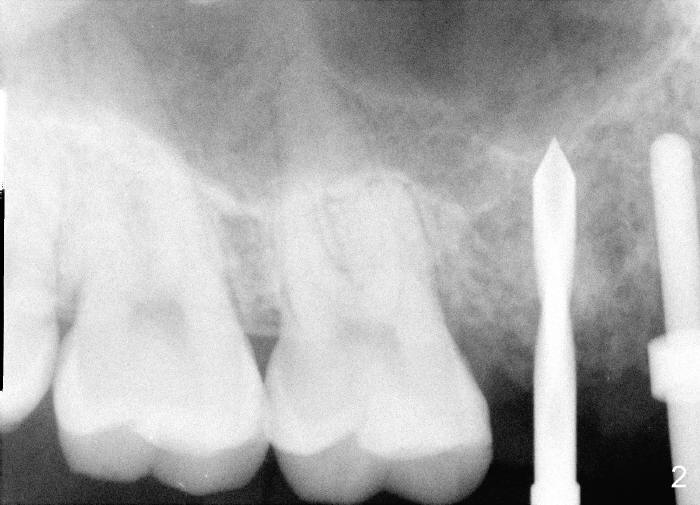

9. Fig.2,3 show pilot drill and guiding pin at the sites of #4 and 5, respectively.  Thanks to our joined effort, the axis of the implant at the site of #4 was corrected from Fig.4 to 6

3. PA device, for lower posterior, use endo device; for upper, regular; for upper premolar, anterior if root and bone are long.  Today the patient’s mouth is small.  No.1 sensor was used with anterior PA device later (Fig.4-6)